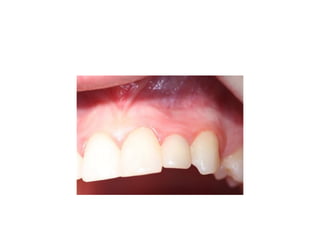

palatal inflammation is noted from

retainer

implants are placed w/in restorative

confines

time of insertion

retainer has been modified

final crowns are delivered